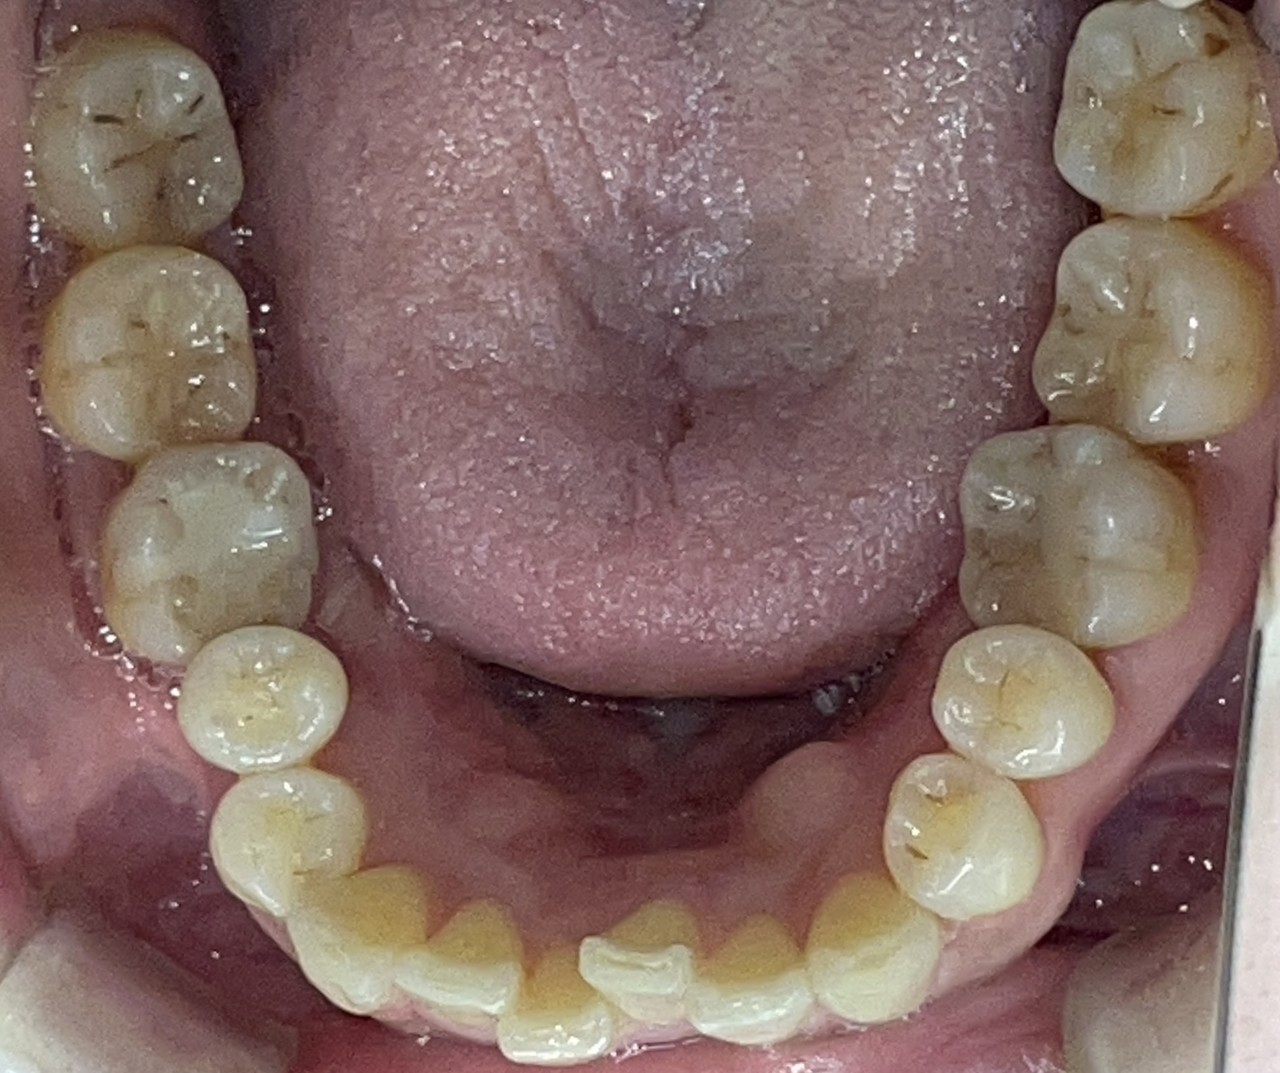

Before

After

矯正の種類 / invisalign GO

年齢・性別 / 40代女性

主訴  /  叢生

治療期間 / 12ヶ月

費用 / 簡易検査 5,000円(税別) 精密検査 30,000円(税別)

両額マウスピース 450,000円(税別)  両額リテイナー料 60,000円(税別)

※マウスピース交換時別途調節料3,000円(税別)

副作用 / 口内炎・歯の移動に伴う痛み・知覚過敏 ※数日で収まる場合が多いです

リスク / 後戻り防止の為、夜のみマウスピースで保定を指示